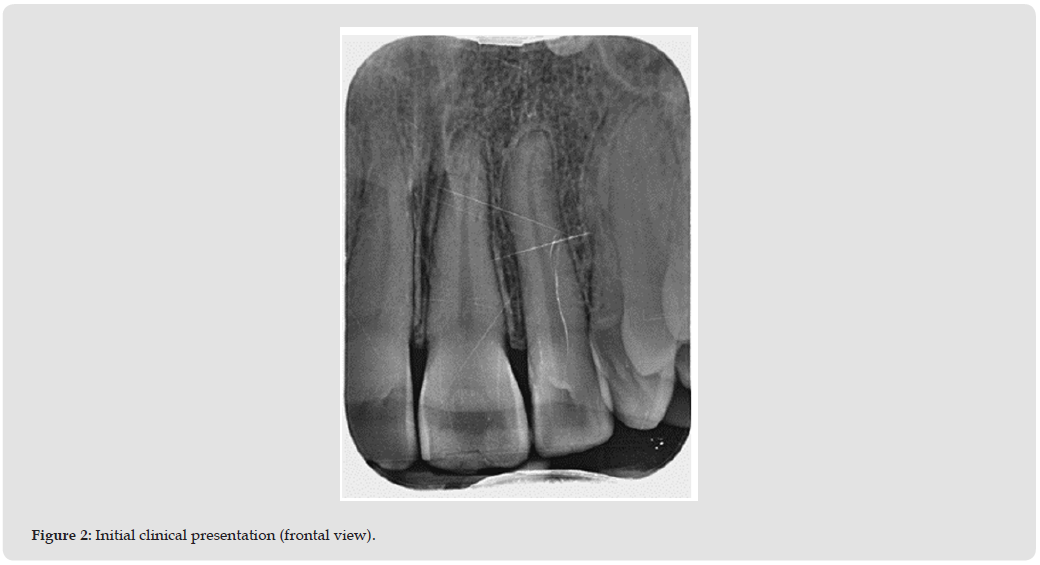

Clinical examination and a periapical radiograph revealed:

- Negative response to vitality testing

- Negative percussion and palpation tests

- Apical radiograph showed pulp horn obliteration and an incipient periapical lesion (Figures 1 & 2).

These findings confirmed pulp necrosis and suggested hemorrhagic degradation products (hemoglobin breakdown) as the origin of the pink discoloration [6-10].